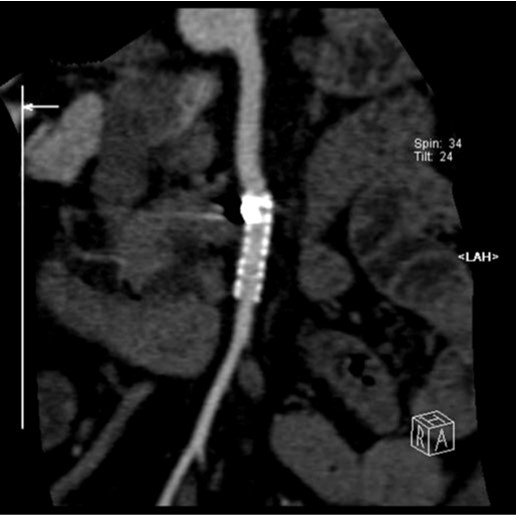

2009년 3월 복부 CT에서 SMA 기시부 하방 2cm 부위부터 5cm 길이의 편심성 혈전이 관찰되고 있으며 혈전이 있는 부위의 동맥 직경이 커져 있음(Fig. 1). 대동맥이나 분지 동맥에 동맥경화증의 소견은 관찰되지 않으며 심장초음파 및 심전도 검사에서 혈전이나 심방 세동은 없었음. CT 소견과 증상을 기준으로 spontaneous isolated SMA dissection으로 진단하였으며 창자의 허혈 소견이 보이지 않고 통증도 악화되지 않아 보존적 치료를 하였음. 2009년 6월 추적 CT에서 false lumen내 대부분의 혈전은 소실되었으나 SMA 기시부 5cm 하방 부위에는 국소적 혈전을 동반한 saccular pseudoaneurysm이 관찰됨. 2009년 8월 시행한 추적 CT에서 pseudoaneurysm의 직경이 2mm 증가함 (Fig. 2). 2009년 9월 시행한 혈관 조영술에서 saccular pseudoaneurysm이 SMA 기시부 5cm 하방부위에 관찰되며 SMA의 국소적 협착이 관찰됨 (Fig. 3). 스텐트와 코일을 이용한 혈관 내 치료 후 시행한 혈관 조영술에서 SMA의 국소적 협착과 pseudoaneurysm은 소실됨 (Fig. 4). 시술 3개 월 후 시행한 추적 CT에서 pseudoaneurysm은 완전히 소실되었으며 SMA는 정상소견을 보임(Fig. 5).

Fig. 2.

Fig. 2. Enhanced CT scan obtained 6 month later reveals improvement of eccentric thrombus, but a saccular pseudoaneurysm is noted in the superior mesenteric artery.